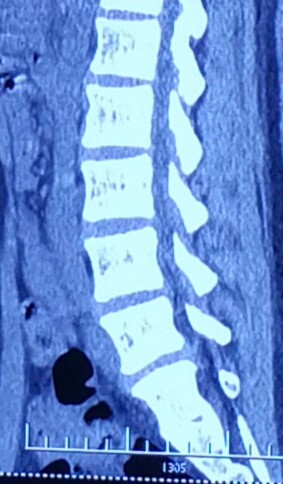

从磁共振片子上看,突出间隙位于腰4、5和腰5骶1,以腰5骶1间隙的椎间盘突出尤为明显,属于左后方的巨大突出,腰5神经根明显被挤压,已经看不清神经的走向,但右侧的神经根影子十分清楚,出现患肢的麻木也就是理所当然的了。目前体检发现左下肢直腿抬高试验40度阳性,加强试验阳性,右侧均为阴性,左侧小腿后外侧及足背外侧也有片状皮肤感觉减退区域,左侧跟腱反射微微有些减弱,右侧是正常的,看得出,骶1神经根是受到了一定的伤害。